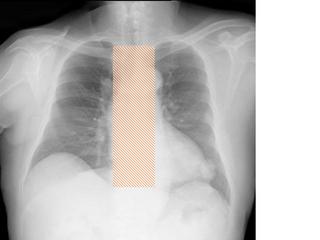

縦隔の所見

縦隔を見るときに、ボーッと見ていては所見を見逃します。

各種の線を追いかけていきましょう。

こちらを見て下さい。